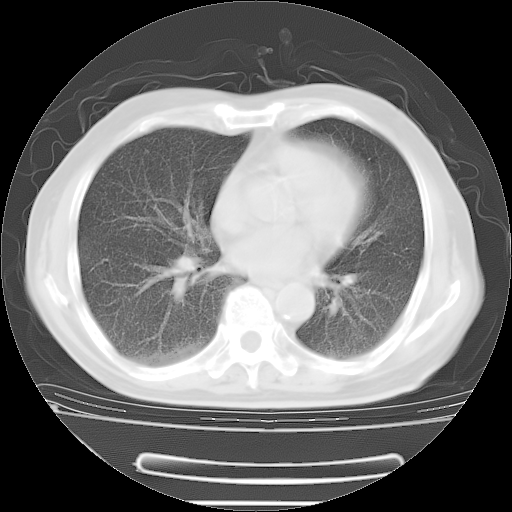

今天复查肺部CT,发现双肺广泛磨玻璃样改变。所以我把3月19日和5月9日相隔50天的肺部CT上传。请大家会诊。

5月9日肺部CT(在4月27日齐鲁医院肺部CT描述部分肺组织磨玻璃样改变,12天后肺组织广泛磨玻璃样改变)

2009年5月9日肺部CT

大致读了系列胸部CT:纵隔窗无明显异常,肺窗:从4、27至今:主要是双肺中下野外带可见毛玻璃样改变,目前处于急性肺泡炎阶段,至于原因考虑1、结替组织或胶原血管性疾病所致?2、恶性疾病如恶组在肺部所致的表现或细支气管肺泡癌?3、药物或其它原因如肺蛋白沉着症所致肺泡炎目前不太可能?总之,明天就去请我院的呼吸科、感染科、血液科和临免专家会诊哈。